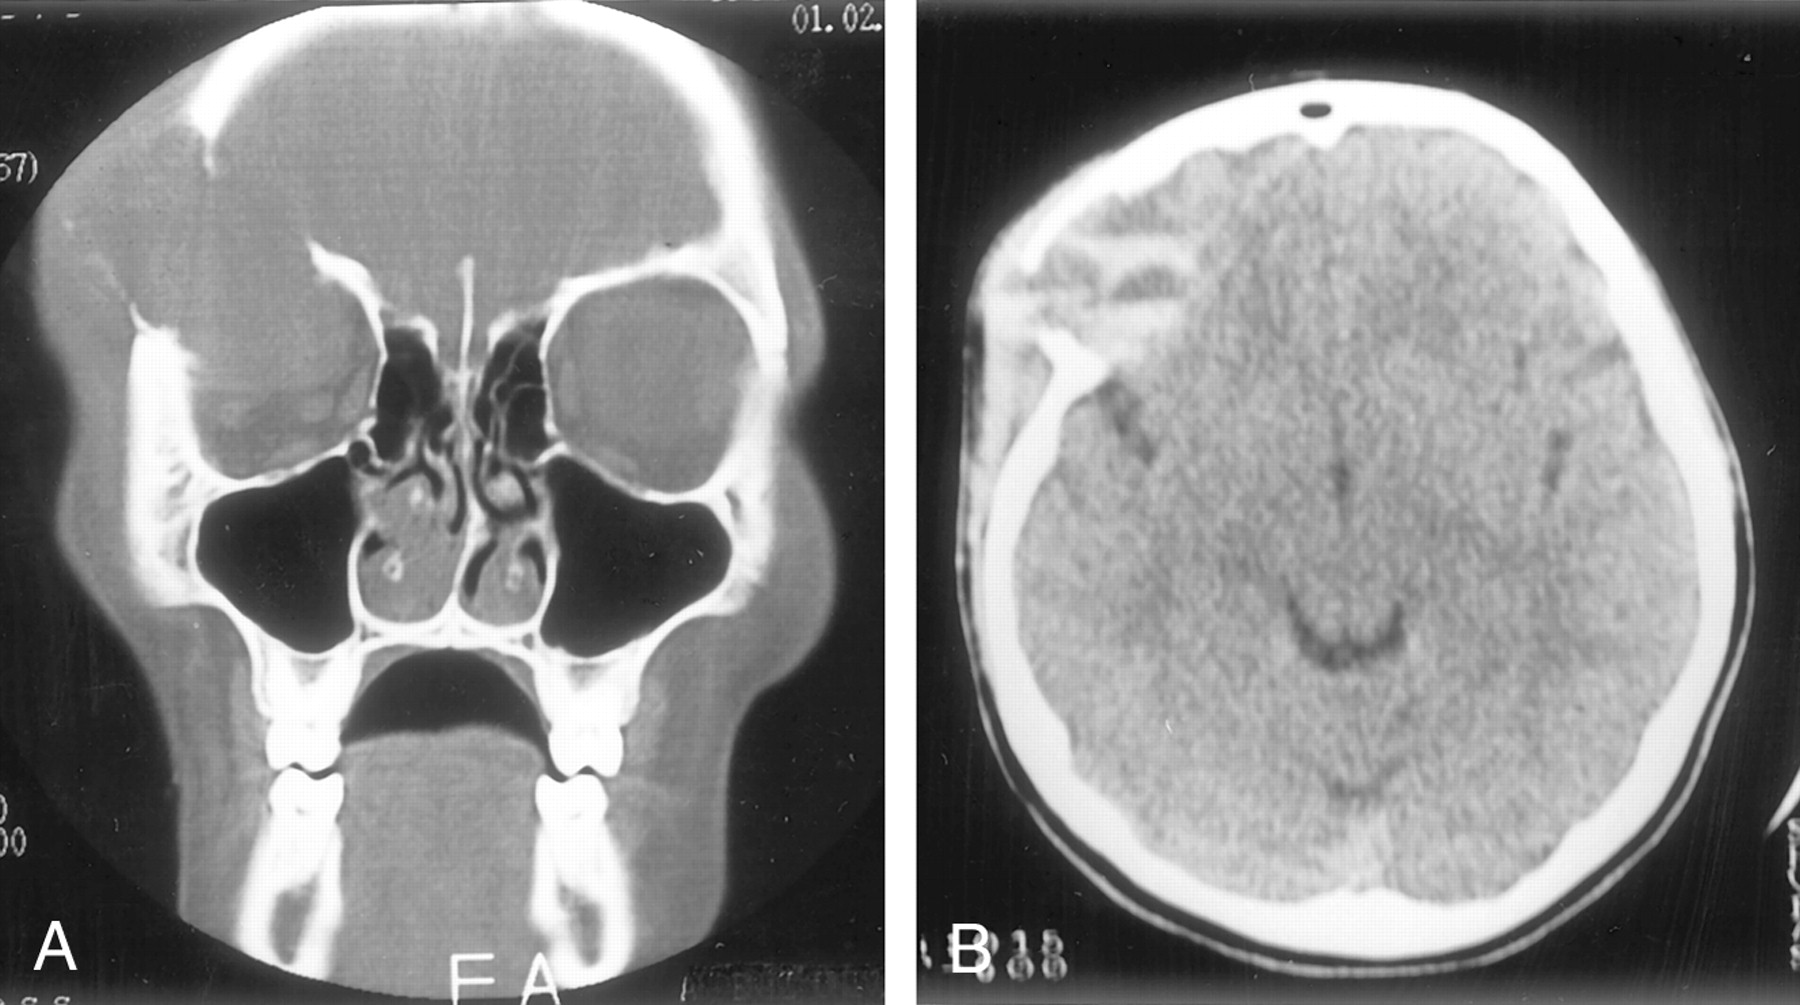

A 13-year-old female adolescent had rapidly growing, painful swelling in her right frontal region and diplopia over a 2-month period. She had no history of trauma or surgery. Physical examination revealed a firm, fixed mass situated just superior and posterior to the right orbital rim. Exophthalmos was present on the right. The lateral gaze of the right eye was restricted, but visual acuity was normal. On coronal and axial CT scans, a multiloculated mass with fluid-fluid levels was found. Bone destruction was present in the superior, lateral, and posterior walls of the right orbit (Fig 1). T1- and T2-weighted imaging revealed variable signal intensities of fluid-fluid levels, consistent with blood degradation products. The walls of the cystic spaces and surrounding rim showed contrast enhancement. The mass was compressing the optic nerve and ocular muscles inferomedially (Fig 2). A cystic mass, approximately 4.5 × 3 × 3 cm in size and containing brown-yellowish fluid, was surgically removed. Histopathologic analysis revealed multiple blood-filled cystic spaces. The borders of these spaces were lined by osteoclast type multinucleated giant cells, bone, and fibrous tissue. Endothelial cells were not present. These findings were consistent with those of an aneurysmal bone cyst (Fig 3).

Bone destruction in the superior, lateral, and posterior walls of the right orbit.

A, Coronal CT scan obtained with bone window settings shows an orbital mass causing bone destruction and displacing the orbital structures.

B, Axial non–contrast-enhanced CT scan shows multiloculated mass with fluid-fluid levels.